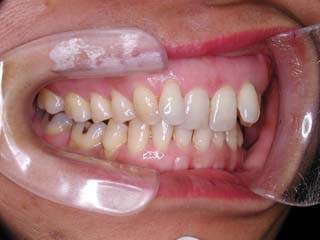

主訴:上の歯が出ている

診断名:顎関節症、下顎左右5欠損を伴う骨格性上顎前突

年齢:35歳

使用した主な装置名:TPB、マルチブラケット装置

抜歯/非抜歯および抜歯部位:非抜歯

治療期間:動的処置2年、経過観察3年

費用の目安:保険適応 自己負担金として30~50万

リスク、副作用:外科手術によるリスク、マルチブラケット治療に伴う歯根吸収など偶発症が発生するリスクがある。

強い骨格性の上顎前突が見られます。しばしば、口腔内所見では骨格のズレを歯の補償的な傾斜などでカムフラージュさせているため、あまり大したことのないズレにしか見えない事があります。また、上顎前突の場合は、下顎が関節の位置で知らず知らずのうちに前方へ大きく偏位させて噛んでいる事が多いです。このような場合は、咬合器に装着してみて初めて、治療方針が見えてくるかもしれません。どのような不正咬合であれ、大きなズレに対しては、外科的に骨のズレを改善する治療が理にかなっています。前後のズレ、垂直のズレと条件が重なってきた場合、より外科矯正での改善が望ましいでしょう。

一般的な外科矯正治療の流れは、術前矯正・外科矯正・術後矯正・保定治療と移行します。術後矯正では、手術後に僅かに見られる後戻りに対する処置や、刻々と変化する額関節の環境に対応して調節を続けます。特に大きな問題が無ければ6か月程度で保定治療に移行します。